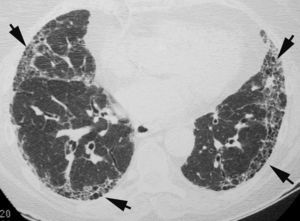

Engrosamiento de los septos interlobularesEl engrosamiento de los septos interlobulares de localización central produce imágenes lineales de varios centímetros de longitud. Los septos localizados en la periferia y perpendiculares a la superficie pleural dan lugar a las llamadas líneasB de Kerley. El engrosamiento septal puede ser liso o nodular (fig. 1). El engrosamiento liso se produce principalmente en el edema intersticial pulmonar y en la diseminación linfática pulmonar de algunos tumores. En la linfangitis carcinomatosa, el engrosamiento septal podrá se liso o nodular. El engrosamiento septal nodular se observa también en el sarcoma de Kaposi, el linfoma y la sarcoidosis.

Engrosamiento intersticial intralobularSe caracteriza por la presencia de una fina trama reticular que se extiende desde las estructuras peribroncovasculares del centro del lobulillo hasta los septos interlobulares, con una morfología «en tela de araña» (fig. 2). Este patrón aparece en la linfangitis carcinomatosa y en el edema pulmonar. También está presente en la fibrosis.